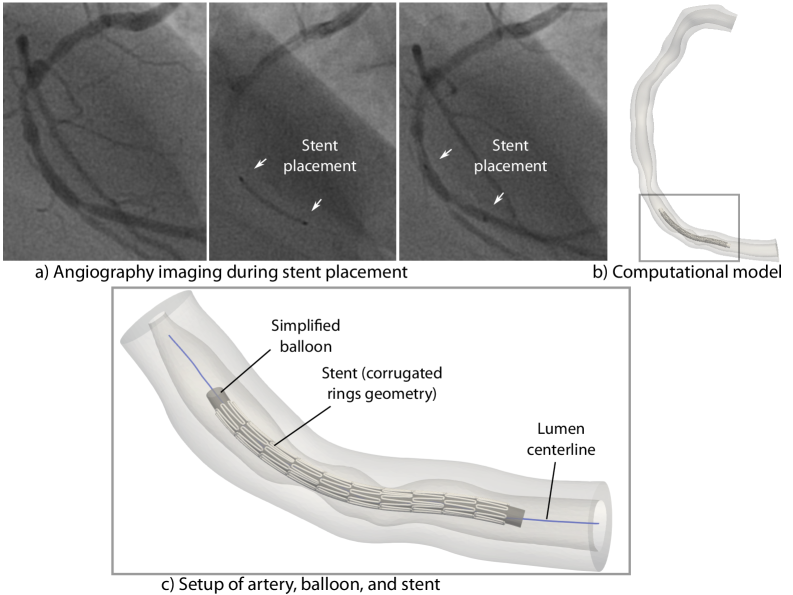

The stent is modeled using reduced-dimensional Simo-Reissner beam elements, which are well suited to represent the slender struts and bending-dominated deformation mechanisms governing the radial expansion. Elasto-plastic behavior is included to capture the permanent deformation responsible for the vessel support after stenting. The stent geometry is based on the “corrugated rings” design (see, e.g., 9), and modeled with BeamMe Authors . It is shown in Fig. 4c). The edges are rounded, resulting in a more realistic expansion shape compared to Datz et al. [2025]. The balloon catheter modeled using a three-dimensional finite element formulation and is represented by a simplified, thin-walled elastic model that reproduces realistic inflation behavior while substantially reducing computational cost. The stenting device, i.e., balloon and stent, is positioned based on the coronary angiography imaging data, shown exemplarily for one lesion in Fig. 4. The initial configuration of the stenting device is assumed to be stress-free.

Refer to caption

Figure 4: Stent placement in the computational model guided by the angiography imaging during the intervention